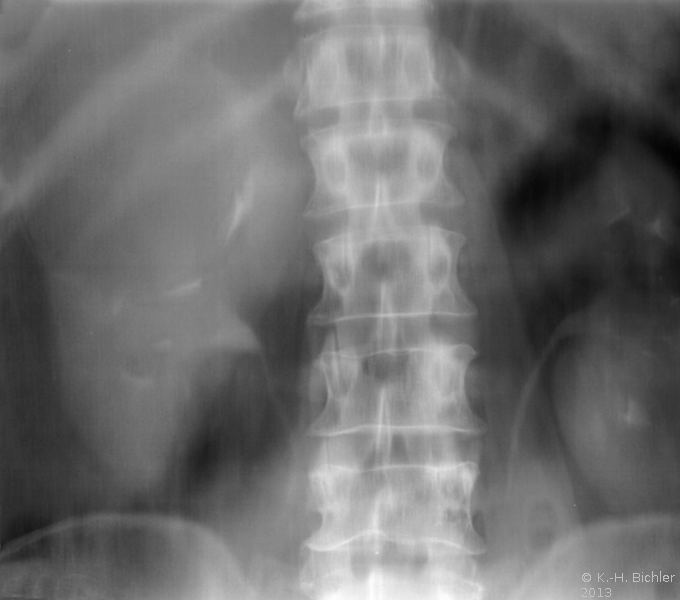

Die Abklärung bei komplexen zystischen Prozessen ist im Algorithmus aufgezeigt (Abbildung 2).